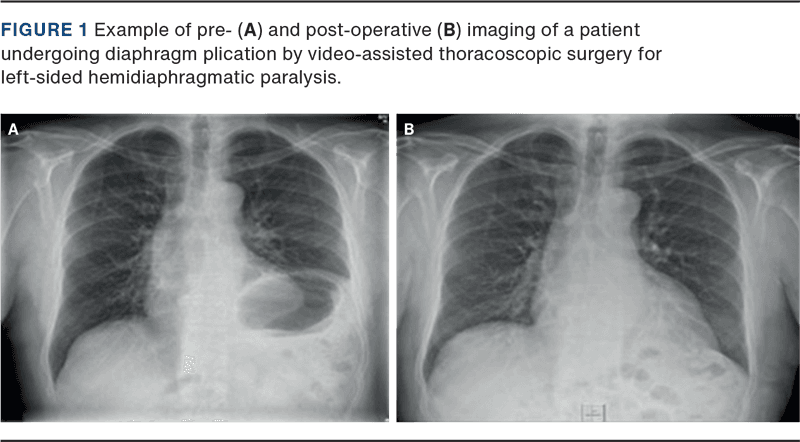

This small case series demonstrates significant improvement in pulmonary function (FVC and FEV1) and respiratory symptoms following VATS-based DP (Figure 1). This is consistent with the existing literature [3, 5, 9, 11, 13], which mainly includes case reports or small case series. Freeman et al. compared VATS, open surgery and conservative treatment in a cohort study, reporting improved dyspnoea and pulmonary function at a six-month follow-up [6], with sustained increases in FVC and FEV1 of 19% and 23%, respectively, after 57 months [11].